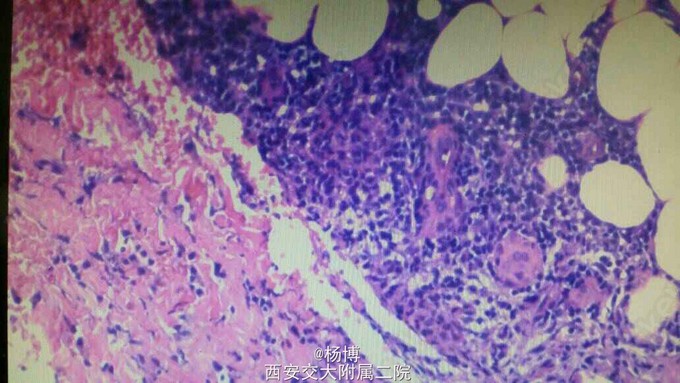

病理诊断为结节性红斑 诊疗计划:完善血尿粪常规,肝肾功能,胸片,查血沉,自身抗体谱测定,风湿三项,排除其他结缔组织病,排除硬红斑,对因治疗,给予复方甘草酸铵,喜炎平等抗炎对症治疗

卧床休息,抬高双下肢,该病需要于结节性血管炎鉴别,后者多发于老年女性,皮损多为大小不一的散在皮下结节,反复发作,好发于小腿屈侧,分布不对称